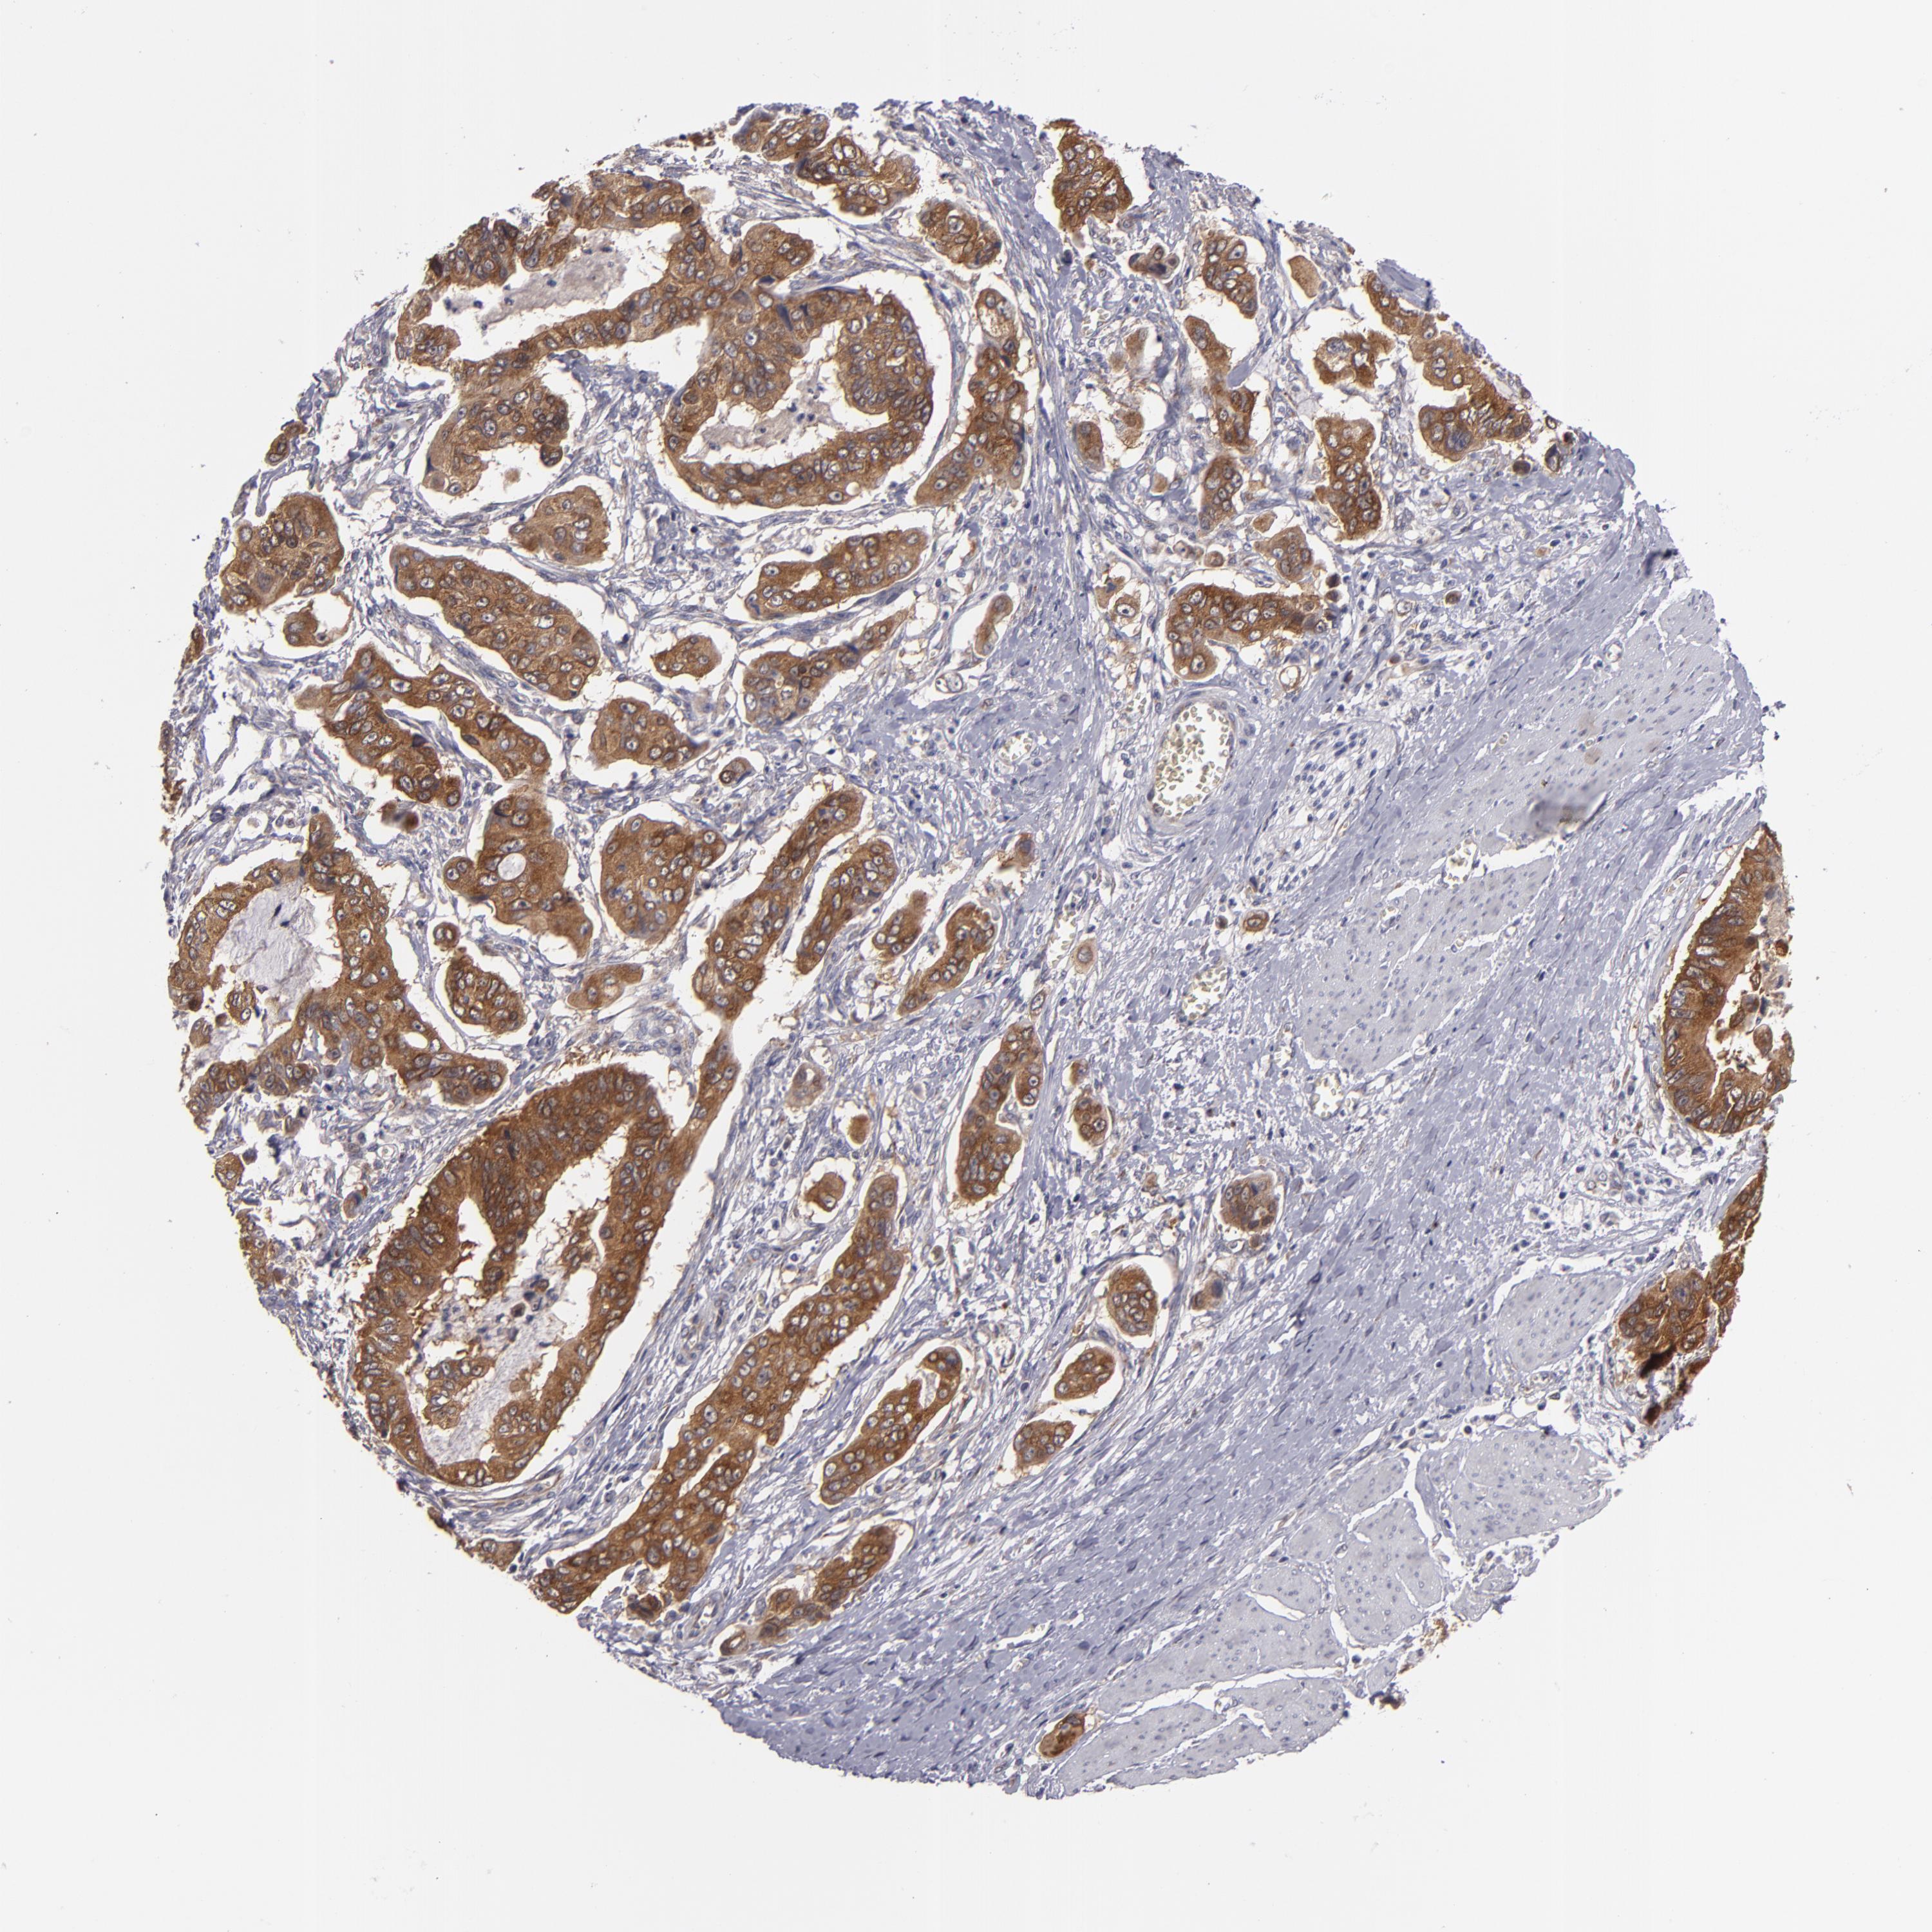

STOMACH CANCER - Protein expressioni

A mouse-over function shows sample information and annotation data. Click on an image to view it in a full screen mode. Samples can be filtered based on level of antibody staining by selecting one or several of the following categories: high, medium, low and not detected. The assay and annotation is described here.

Note that samples used for immunohistochemistry by the Human Protein Atlas do not correspond to samples in the TCGA dataset.

Antibody stainingi

Antibody staining in the annotated cell types in the current human tissue is reported as not detected, low, medium, or high, based on conventional immunohistochemistry profiling in selected tissues. This score is based on the combination of the staining intensity and fraction of stained cells.

Each image is clickable and will lead to virtual microscopy that enables deeper exploration of all samples and also displays staining intensity scores, fraction scores and subcellular localization as well as patient and tissue information for each sample.

Antibody HPA001871

Antibody HPA001919

Staining

High

Medium

Low

Not detected

Intensity

Strong

Moderate

Weak

Negative

Quantity

>75%

75%-25%

<25%

None

Location

Nuclear

Cytoplasmic/membranous

Cytoplasmic/membranous,nuclear

Adenocarcinoma, NOS